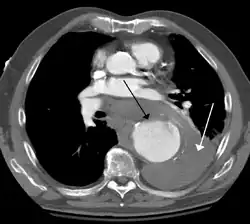

Contrast enhanced CT of a ruptured large (7 cm) thoracic aneurysm, with black arrow indicating the aorta, and white arrow blood in the thorax

The principal causes of death due to thoracic aneurysmal disease are dissection and rupture. Once rupture occurs, the mortality rate is 50–80%. Most deaths in patients with Marfan syndrome are the result of aortic disease.